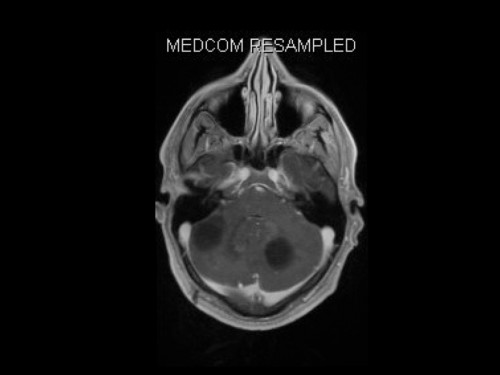

3. Schwindel und Kopfschmerzen, 3 Jahre nach Phäochromozytom-Resektion

Schwindel und Kopfschmerzen, 3 Jahre nach Phäochromozytom-Resektion

19-jähriger Mann. Er klagt seit mehreren Wochen über Schwindel und Kopfschmerzen. Im Alter von 16 Jahren sind er und sein Zwillingsbruder an einem Phäochromozytom operiert worden.